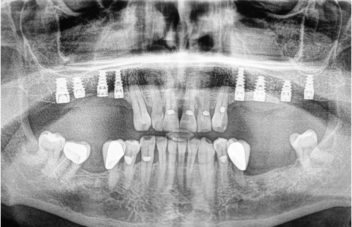

PORÓWNANIE: NATYCHMIASTOWE OBCIĄŻENIE A KLASYCZNY PROTOKÓŁ